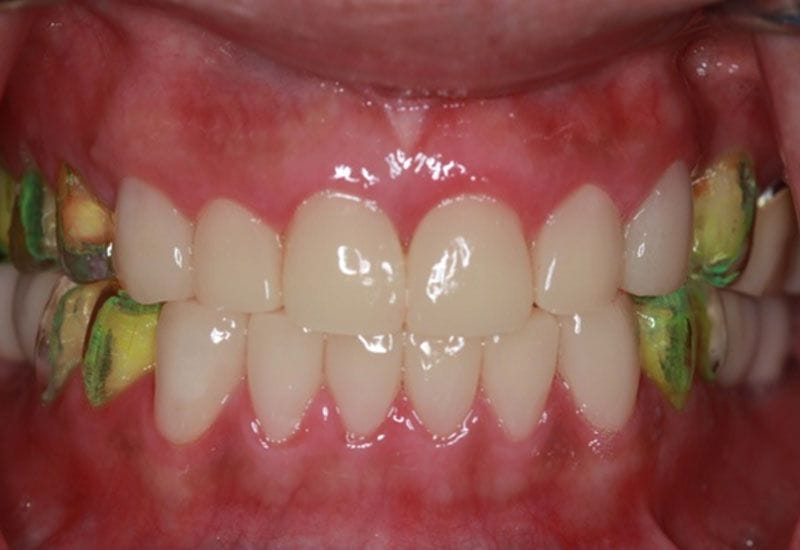

接著,陳柏均醫師以此蠟型高度為病人進行欲重建牙齒的修磨和臨時假牙,病患之後將配戴此臨時假牙做約1-3個月的試戴觀察。

臨時假牙階段非常重要,此階段的目的在於觀察牙齒經過修磨後,咬合是否適應,以及牙齒神經是否敏感或疼痛

如圖7

圖7